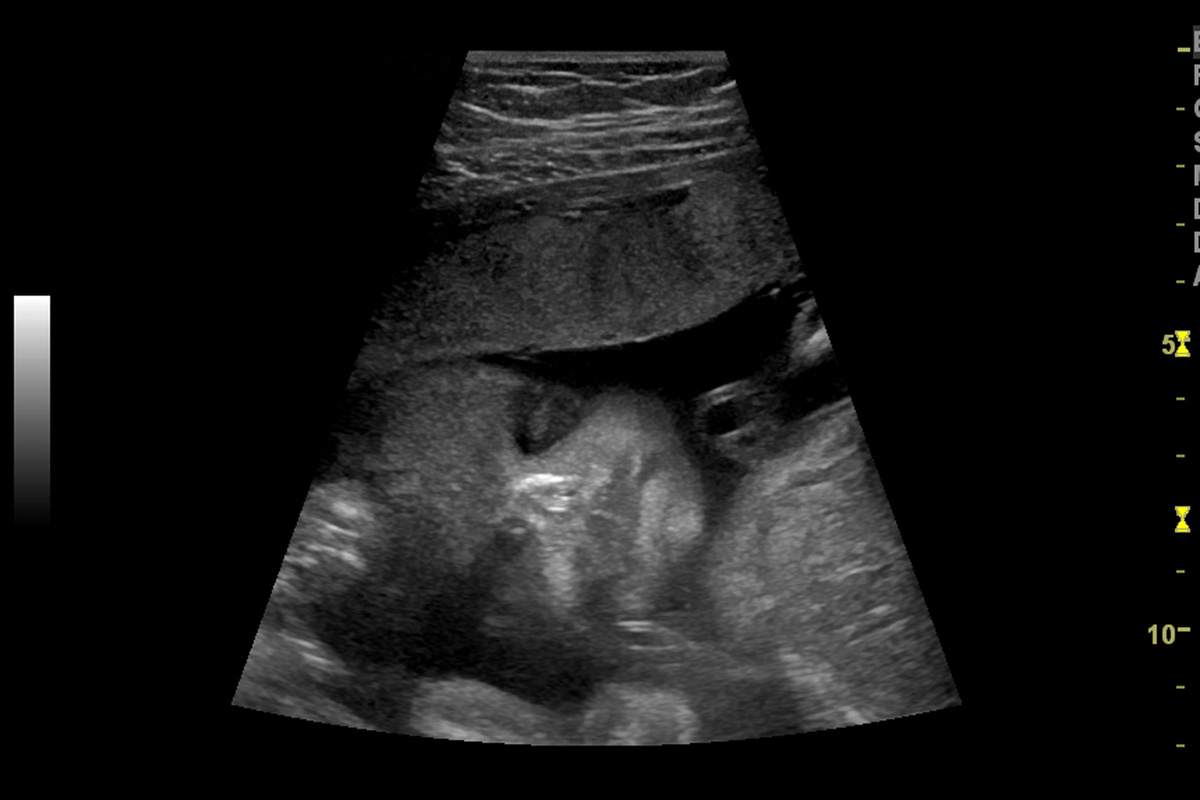

Малыш еще очень маленький: к началу 4-го месяца его рост не превышает 8 см, вес — 15−20 г, а к концу этого периода вырастает до 13−15 см и 70−90 г. Но, несмотря на свой размер, плод уже напоминает маленького человечка!

Плод в 4-й месяц беременности